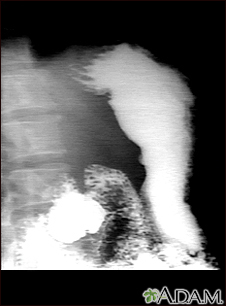

This is an example of a procedure called an upper GI series. The person swallows a substance called barium which allows for illumination of the organs in question. In this case, an ulceration is present in the stomach, seen on the right of the screen. This method is a means of diagnosing stomach ulcers as well as other anomalies along the upper gastrointestinal tract.